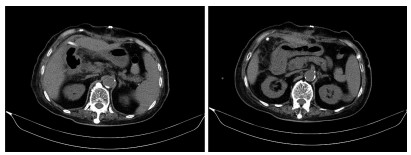

Acute pancreatitis caused by a hematoma in the duodenal wall: A case report

Mengran ZHU, Shanshan JIANG, Tingting YU, Yun BAI, Dingxin WANG, Linping SHI

2022, 38(3): 639-642. DOI: 10.3969/j.issn.1001-5256.2022.03.029

Abstract(1350) HTML (248) PDF (3475KB)(62)

Abstract: